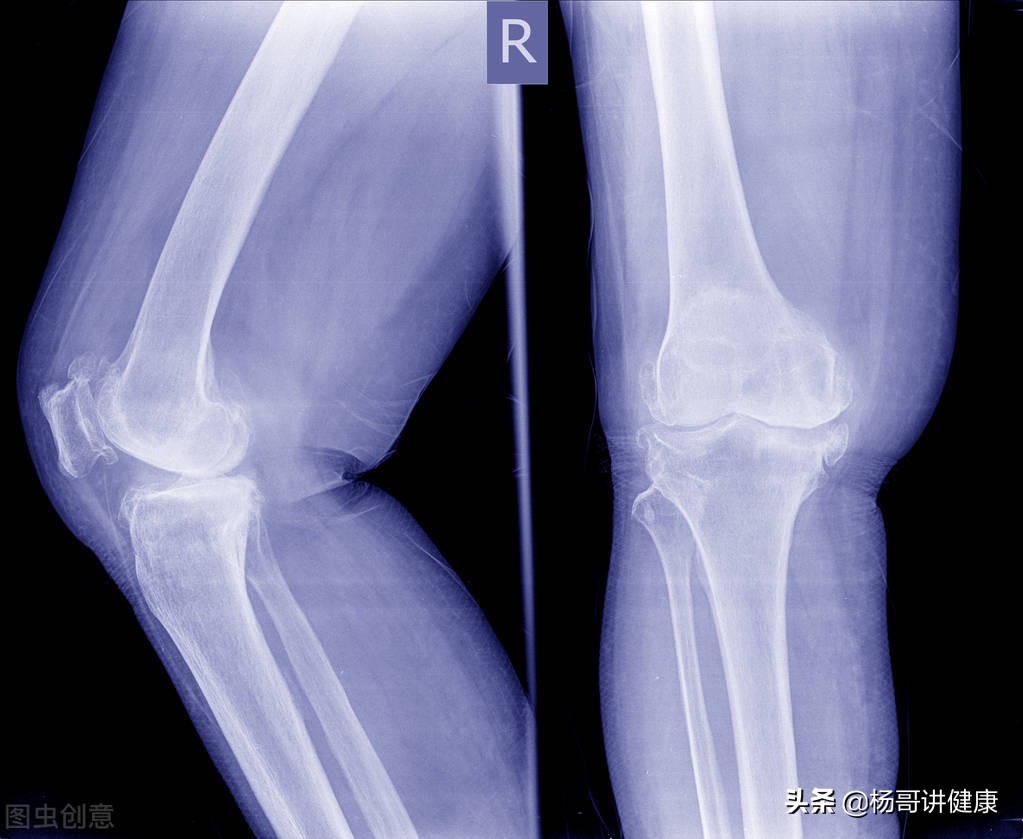

#膝关节长骨刺怎么治疗?#当20年前有人问膝关节长骨刺怎么治疗时,还是一种普遍现象,那个时候X光片还是一家独大,用它就能照出骨刺来。而如今,价格便宜的X光片几乎无人问津,即使CT也被冷落一旁,核磁已经从当时的“王谢堂前燕”,飞入了“寻常百姓家”,管你是拉车的、烧碳的,还是搞电气焊的,只腰你膝关节疼,上来就是核磁,出来的都是半月板撕裂、交叉韧带断裂、关节腔积液、髌骨软化等等,什么狗屁骨刺,早OUT了吧,你这病也太落后了吧!